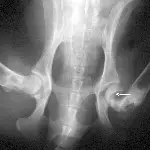

Figure 1A. Hairline fracture of the fibula.

Figure 1B. The fracture is more clearly seen 4 weeks later following bone resorption and periosteal proliferation at the fracture site.